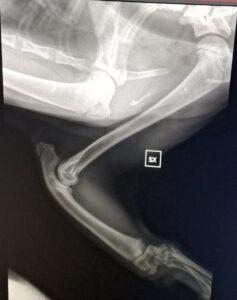

Denn inzwischen wurde Pino auf Sardinien untersucht und geröntgt. Es war sehr stark zu erwarten, dass es sich um eine angeborene Anomalie handelt. Und dies ist auch so. Pinos „Ellenknochen“ (Radius) fehlen auf der einen Seite ganz, auf der anderen Seite ist er unterentwickelt. Das führt dazu das seine Füßchen mit den Ellenbogen nicht stabil verwachsen sind und die Gelenke nicht festsitzen. Dadurch wachsen auch die Knochen nicht entsprechend und haben krankhafte Veränderungen.

Der kleine Mann ist eine „Känguru-Katze“, seine verkürzten Vorderbeine wird er nie richtig belasten können, so wie es im Moment aussieht. Ein normales Katzenleben in Freiheit ist für ihn unmöglich. Gott sei Dank zeigen sich aber keine andere Anomalien in seiner Anatomie.